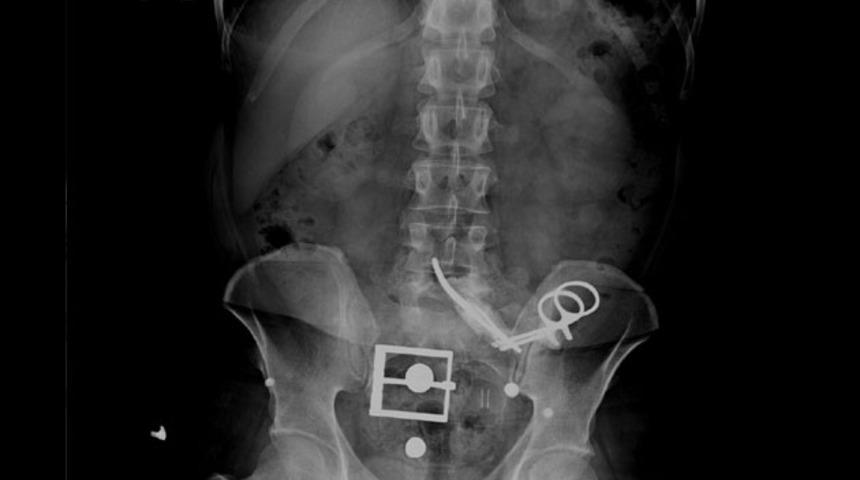

Adapazarı'nda yaşayan F.D. (42) adlı erkek, dalağının alındığı ameliyatta karnında 13 santimlik makasın unutulduğunu 23 yıl sonra bel ağrısı şikayeti ile gittiği hastanede öğrendi. Makas yapılan operasyonla çıkarılırken, F.D.'yi o dönem ameliyat eden doktorun birkaç yıl önce yaşamını yitirdiği belirtildi.

Adapazarı'nda F.D, 1995 yılı Mayıs ayında 19 yaşındayken rahatsızlığı nedeniyle Sakarya Devlet Hastanesi'ne gitti. Yapılan tetkiklerin ardından ameliyat edilen F.D.'nin dalağı alındı. Evlenip, bir çocuk sahibi olan F.D., bu tarihten sonra birçok kez hastaneye gitti, ancak karşılaştığı sağlık sorunlarında doktorlar MR veya röntgene gerek duymadı. Aradan geçen 23 yıl sonra, 1 Nisan'da bel ağrısı şikayetiyle Sakarya Üniversitesi Eğitim ve Araştırma Hastanesi'ne giden F.D.'yi muayene eden doktor, durumdan şüphe edince MR istedi.

Doktor ayağında platin olduğunu ve cihaza yaklaşamayacağını söyleyen F.D.'yi bu kez röntgen çekilmesi için yönlendirdi. Röntgene bakan doktor, karın bölgesinde 13 santim uzunluğunda ameliyat makasının olduğunu tespit etti. Makasın, F.D.'nin 23 yıl önce geçirdiği dalak ameliyatında unutulduğu ortaya çıktı. F.D.'nin karnındaki makas, başarılı bir operasyonla alındı. F.D.'nin durum fark edilmeden önce MR için cihaza girmiş olması durumunda makasın iç organlarını parçalayabileceği belirtildi.